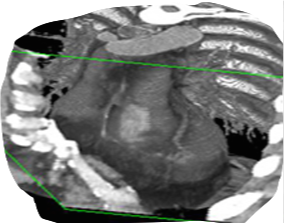

Believe it or not, this is actually an image of my heart! This was obtained by an x-ray technique known as computed axial tomography, better known as a CAT scan. In this form of the technique, x-ray images are collected in a 360 degree circle around the body through the length of the chest cavity. Special computer programs then combine and resconstruct the images into a three dimensional picture that shows the structure in great detail. What other surrounding structures can you identify?